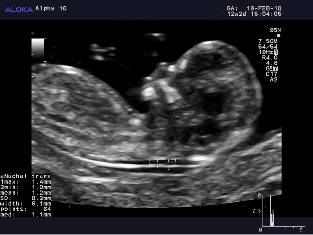

Semi-auto NT test on an Aloka Alpha 10 system

Although ALOKA’s Automated NT algorithm is currently under test

and still need to be formally peer-reviewed before it becomes an

accepted practice, current results look extremely promising and

indicate the potential benefits of this approach.